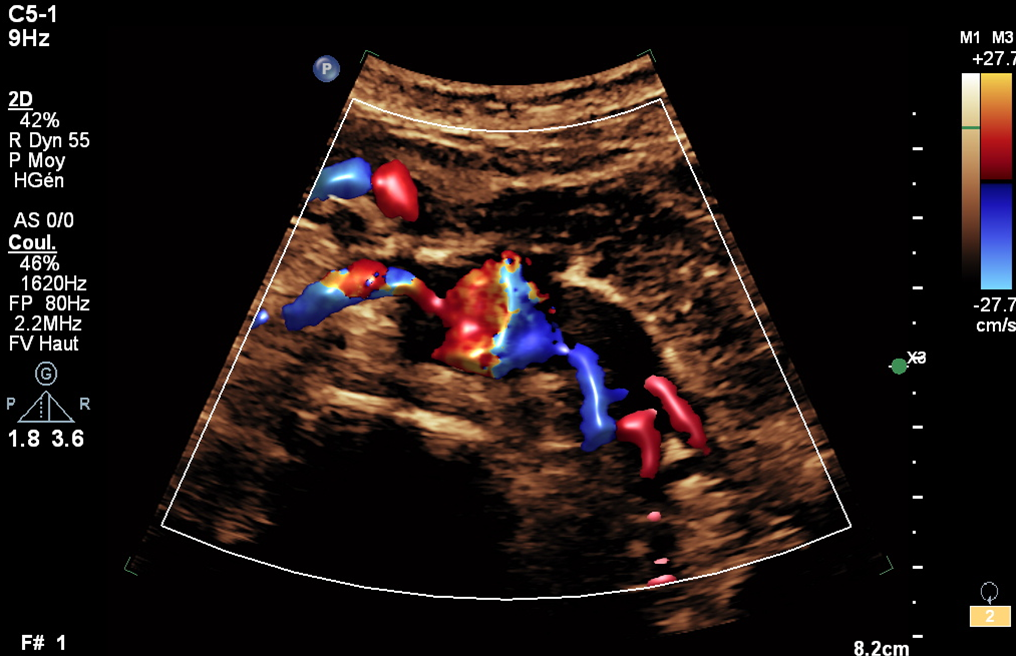

Renal Artery Doppler in Secondary Hypertension: Case of Ostial Right Renal Artery Stenosis